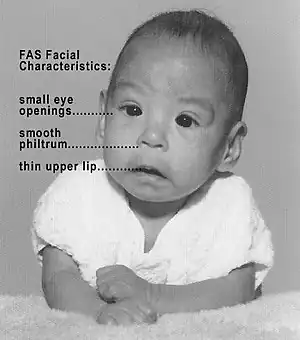

In addition to the neurotoxic effects of ethanol in mature organisms, chronic ingestion is capable of inducing severe developmental defects. Evidence was first shown in 1973 of a connection between chronic ethanol intake by mothers and defects in their offspring.[106] This work was responsible for creating the classification of fetal alcohol syndrome, a disease characterized by common morphogenesis aberrations such as defects in craniofacial formation, limb development, and cardiovascular formation. The magnitude of ethanol neurotoxicity in fetuses leading to fetal alcohol syndrome has been shown to be dependent on antioxidant levels in the brain such as vitamin E.[107] As the fetal brain is relatively fragile and susceptible to induced stresses, severe deleterious effects of alcohol exposure can be seen in important areas such as the hippocampus and cerebellum. The severity of these effects is directly dependent upon the amount and frequency of ethanol consumption by the mother, and the stage in development of the fetus.[108] It is known that ethanol exposure results in reduced antioxidant levels, mitochondrial dysfunction (Chu 2007), and subsequent neuronal death, seemingly as a result of increased generation of reactive oxidative species (ROS).[30] This is a plausible mechanism, as there is a reduced presence in the fetal brain of antioxidant enzymes such as catalase and peroxidase.[109] In support of this mechanism, administration of high levels of dietary vitamin E results in reduced or eliminated ethanol-induced neurotoxic effects in fetuses.[8]